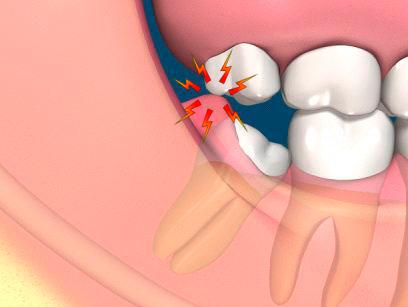

Cualquier diente al salir en la boca, va ” cortando ” poco a poco la encía que se encuentra encima de el para salir a la superficie. Durante el proceso existen pequeñas inflamaciones y en algunos casos infecciones que originaran molestias y dolor. Dependiendo de la persona y de la manera en la que este saliendo la muela, el dolor de muelas sera diferente más suave o muchisimo más fuerte. Hay personas que ni se enteran de cuanto les salen las muelas del juicio , pero la mayoria no tenemos esa suerte y el dolor puede llegar a ser muy severo.

Existen casos debido a que el diente no tiene suficiente espacio para salir o no esta saliendo en la posición correcta , parte de encía se queda cubriendo la muela. Este trozo de encía es una de las mayores molestias de las muelas del juicio pudiendo inflamarse e infectarse , causando una pericorinaritis

El mayor problema es la falta de espacio, la muela del juicio busca una manera de salir y acomodarse , pero muchas veces no puede. Esto conlleva que la muela salga mal posicinada o no salga completamente o lo que es peor que salga dañando las muelas vecinas. Debido a esto se acumula más suciedad en esa zona por lo que causan más problemas.